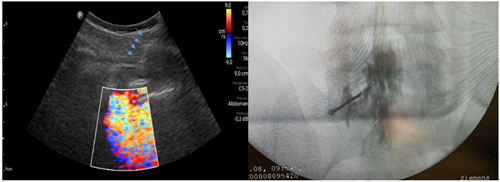

Pacientes y métodos: Un total de 25 pacientes con dolor radicular lumbosacro fueron seleccionados para recibir inyecciones epidurales interlaminares de esteroides en posición decúbito dorsal, utilizando la técnica ecoguiada en plano, en tiempo real, en eje corto o transversal. En todos los casos, un epidurograma de control fue realizado previo a la inyección de la solución de esteroides. El rendimiento de la técnica fue estudiado mediante la tasa de éxito de la misma, entendido como éxito a la obtención de un epidurograma sin necesidad de abandonar la técnica ecográfica en un tiempo menor a 10 minutos. El rendimiento del procedimiento fue estadísticamente evaluado por el método de la suma acumulativa (CUSUM), y la curva de aprendizaje aplicando este método fue construida.

Resultados: La distancia promedio desde la piel al complejo posterior evaluada por el escaneo ecográfico previo al procedimiento fue de 6,7 ± 1,8 cm. De los 25 procedimientos realizados, en 21 se alcanzó el espacio epidural sin ayuda de la fluoroscopia, en un tiempo promedio de 4,8 ± 1,2 minutos. Esto constituye una tasa de éxito del 84 %. En los cuatro procedimientos restantes el espacio epidural fue alcanzado con éxito mediante el uso complementario de la fluoroscopia.

13. Riveros-Perez E, Albo C, Jimenez E, Cheriyan T, Rocuts A. Color your epidural: color flow Doppler to confirm labor epidural needle position. Minerva Anestesiol. 2019;85(4):376-83.

14. Yoon JS, Sim KH, Kim SJ, Kim WS, Koh SB, Kim BJ. The feasibility of color Doppler ultrasonography for caudal epidural steroid injection. Pain. 2005;118(1-2):210-4.

Figura 1

Figura 2